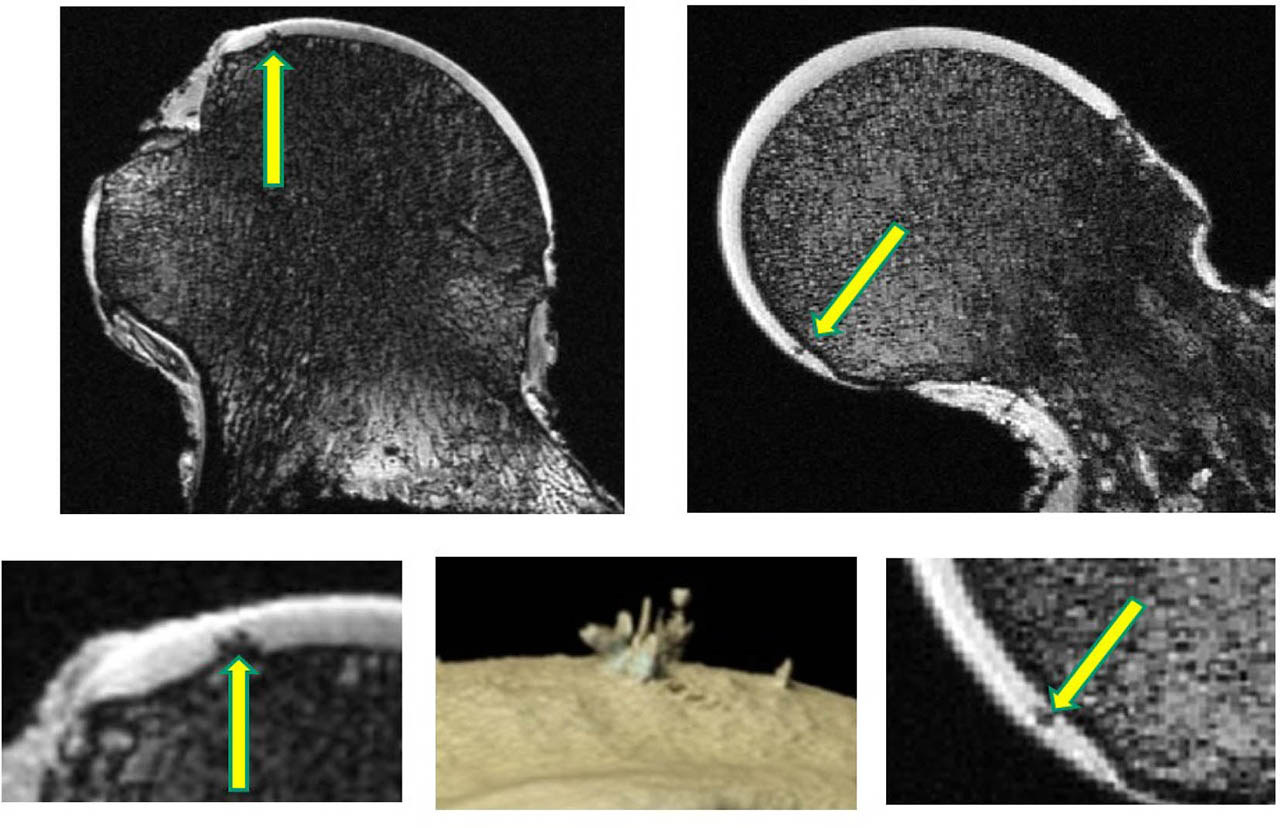

In addition to the progress in finding an effective therapy for AKU, one striking thing that has emerged from research on AKU is that, by studying this rare disease, important lessons have been learnt for more common OA. Rare diseases are a neglected area of study in OA research, but our experience is that greater focus on rare syndromes leads to more rapid advancement, as forecast by 2 of the great English medical scientists of the 17th and 19th centuries, William Harvey and William Bateson [discussed in Ref. 17]. In the extreme phenotypes of Mendelian disorders, disease progression is often rapid and predictable, so it is easier to identify the initiation and subsequent advance of pathological changes. Studies on tissue samples from patients with AKU and from the mouse model of the disease have revealed previously unrecognized microanatomical, cellular, and biochemical features in joints which have been subsequently also recognized in human OA. These include trabecular excrescences in bone[31] and circumferential lamellae in CAC.[32] Of the many lessons learnt from AKU, one that stands out as providing a paradigm shift in our understanding of the pathogenesis of OA and points to new routes for diagnosis and therapy is the identification of high-density mineralized protrusions (HDMPs) (Figure 5). The first discovery of the occurrence of HDMPs in humans came through a study of a severely affected hip joint in an individual with AKU.[33] The patient suffered extreme pain, leading to elective hip surgery. Anatomical examination of his femoral head ex vivo revealed no significant loss of cartilage from the articular surface. Subsequent investigation by micro-computerised tomography (CT), magnetic resonance imaging (MRI), and scanning electron microscopy revealed HDMPs, regions of ultra-dense material arising from the mineralizing front of the CAC and protruding into the hyaline cartilage. The HDMPs appeared to arise from fluid extruded through microscopic cracks in the subchondral plate. The fluid mineralized, forming hard, abrasive structures embedded in the hyaline cartilage and extended up to two-thirds of its thickness. The HDMPs were associated with focal fibrillation directly overlying their site. Moreover, isolated fragments of HDMPs were found in the superficial fibrillated area of the hyaline cartilage (see Figure 6). Nano-indentation proved HDMPs to be stiffer and harder than any other phase in bone organs. Initially, it was thought that these structures were disease specific for AKU, but subsequent studies have revealed that they are present in aging and OA human hip joints. They appear to be analogous to calcified structures previously identified in palmar osteochondral disease of the distal third metapodials in trained Thoroughbred racehorses, a model of overload arthrosis,[34] and subsequently in other equine breeds including the Icelandic horses, which are a good model of genetic OA in a large mammal.[35] The protrusions could play a major role in the destruction of cartilage from the subchondral aspect. HDMPs might also be partially responsible for the discordance between pain and cartilage loss in OA. Their formation constitutes a newly recognized mechanism of joint destruction in AKU and in OA and provides potential targets for drug therapy. Furthermore, the ability to detect HDMPs in joint tissues in situ by MRI holds out the prospect that these recently discovered structures might be a useful imaging biomarker of joint disease progression in AKU and OA.

HDMPs in AKU and non-AKU femoral heads. Upper left panel, MRI slice through the femoral head of a 49-year-old male patient with AKU obtained with an isotropic dual-echo steady-state (DESS) sequence with a resolution of 0.23 mm. Note a region of hypointensity within the hyaline cartilage that corresponds to the position of the HDMPs. Upper right panel, MRI image of a femoral head from an 87-year-old non-AKU male showing a hypointense HDMP (arrow). The lower right and left panels show the HDMPs at higher magnification. The lower central panel shows a 3D micro-computerised tomography (CT) image of HDMPs from the AKU sample (adapted with permission from Boyde et al.[33]). AKU, alkaptonuria; HDMPs, high-density mineralized protrusions.